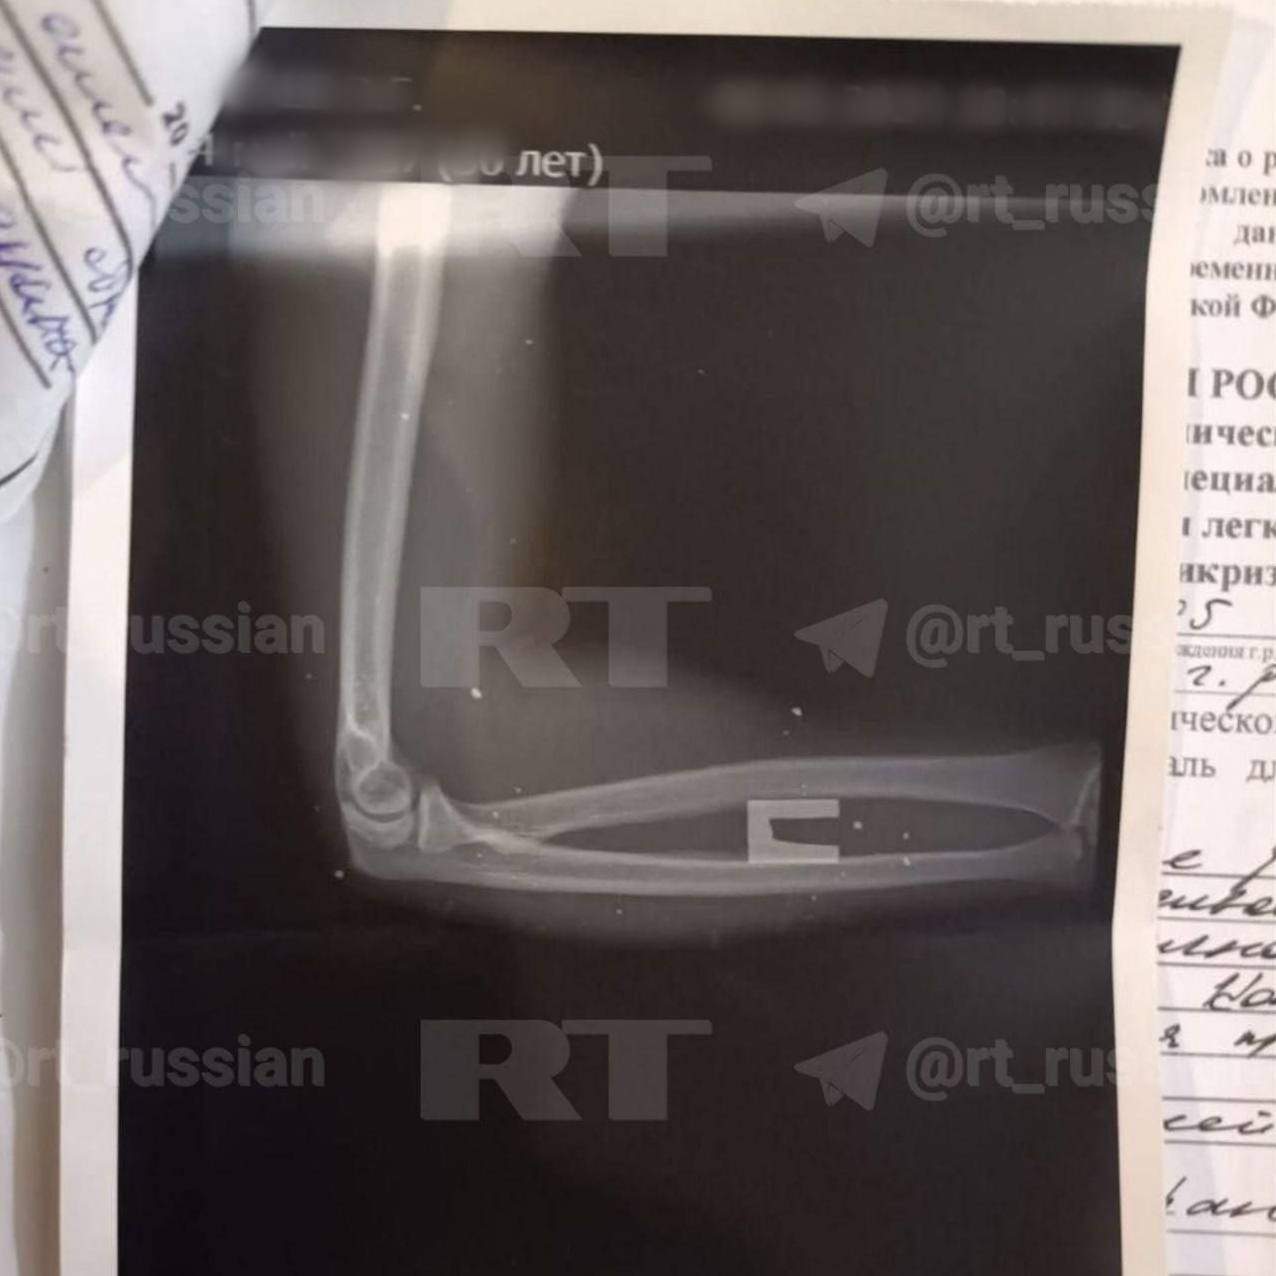

Боец восстановился после полученных в мае 2024-го травм и вернулся в зону СВО. В декабре 2024 года он снова был ранен и сейчас проходит лечение. На последнем фото — рентген, на котором виден осколок в пятке Эльнура.